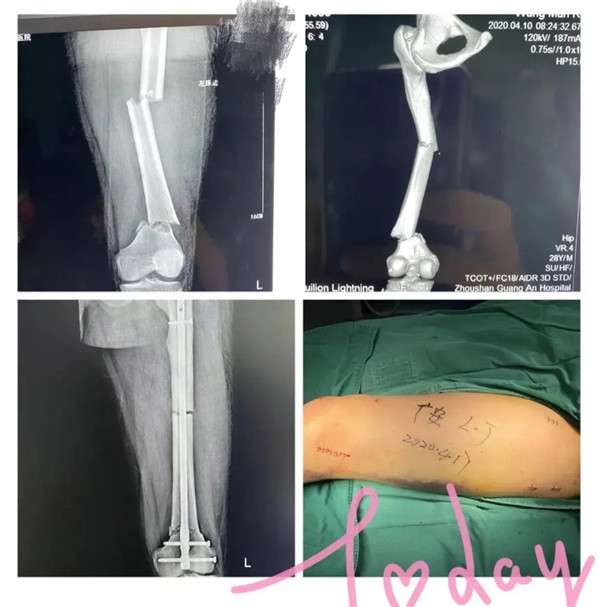

受傷的是家住城北的年輕小伙小王,早上騎電動車去上班速度太快而不慎摔傷。急診醫(yī)生初步檢查,判斷是大腿骨骨折,立即予以拍片檢查。結果顯示:左股骨多段粉碎性骨折。小王左腿股骨竟斷成三截 !須做手術治療。病人和家屬看到片子后,都有點嚇傻了,急得語無倫次,不斷地追問醫(yī)生:“醫(yī)生,這該怎么辦呢?骨頭都斷這樣了,還能接好嗎?……”醫(yī)生趕緊安撫病人和家屬:“到了我們醫(yī)院,您們放心好了。等檢查完善后,我們會盡快施行手術治療的”。小王當即辦理了住院手續(xù)。

4月17日,在經(jīng)過周密的術前準備,小王的身體狀況符合手術指征,并征得家屬同意后,廣安骨科中心副主任羅軍帶領團隊為他實施了閉合復位磁力導航髓內(nèi)釘內(nèi)固定微創(chuàng)手術。

手術在腰部麻醉下進行,術中僅需幾個微創(chuàng)小切口,創(chuàng)傷小,出血少,一個小時后,手術順利完成。術后患者病情很快恢復,生命體征平穩(wěn)。第二天,小王就可以拄拐下地活動并進行康復鍛煉。日前,在醫(yī)護團隊的精心照料下,他已出院回家休養(yǎng)。出院前,小王對著醫(yī)護人員豎起了大拇指:“廣安醫(yī)院的醫(yī)生技術好、態(tài)度佳,真牛!”

據(jù)介紹,此次為小王實施的磁力導航髓內(nèi)釘內(nèi)固定手術以交鎖髓內(nèi)釘技術為基礎,以新興的磁力導航技術為依托,以微創(chuàng)為特點。相比傳統(tǒng)手術,定位更加準確,具有減少手術時間、減少手術出血和創(chuàng)傷、減少術中放射次數(shù),且術后恢復快,傷口小,基本不留明顯疤痕的優(yōu)點,在磁力導航下,實現(xiàn)骨折部位的精準復位?;颊咝g后僅一天就可以開始扶拐下地活動并進行康復鍛煉。